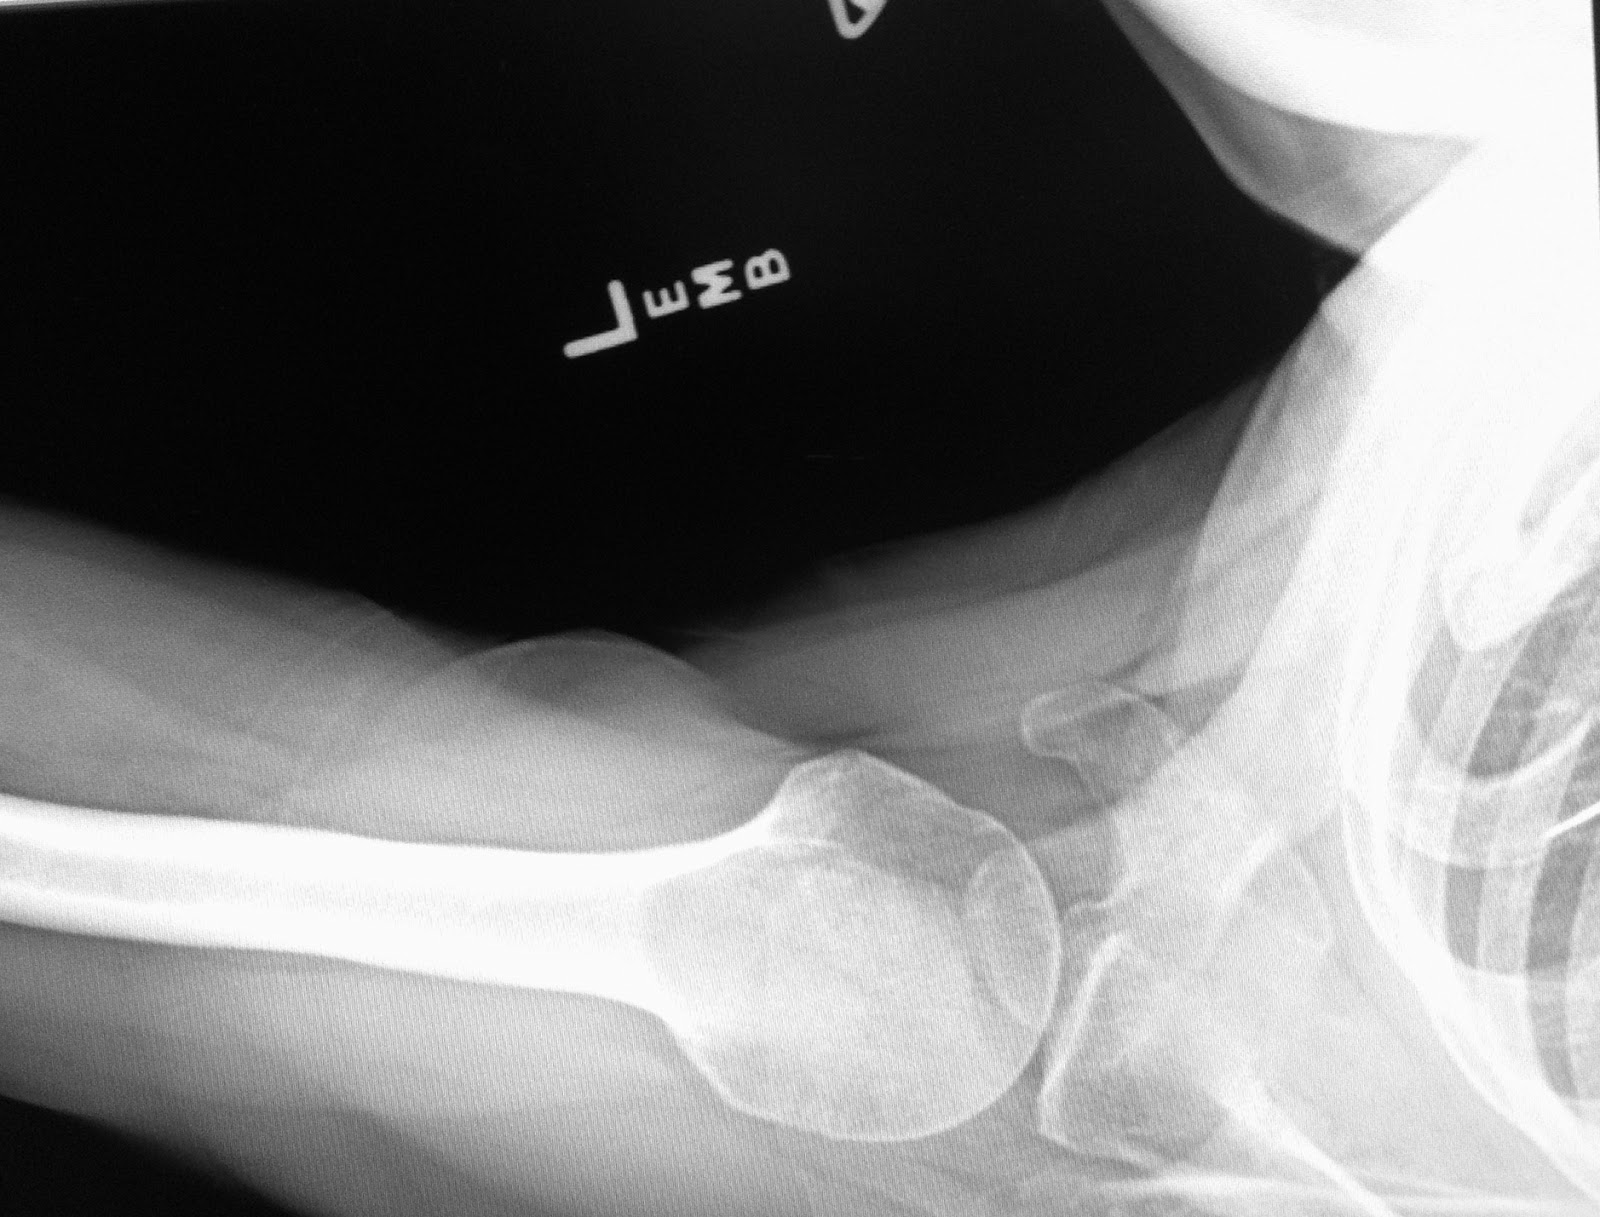

Xray film of primary frozen shoulder or adhesive capsulitis of Asian female patient Stock Photo Adhesive Capsulitis On X Ray Adhesive capsulitis will be used in these guidelines to describe both primary idiopathic adhesive Adhesive capsulitis, commonly referred to as frozen shoulder, is a debilitating condition characterized by progressive pain and limited. Adhesive capsulitis or “frozen shoulder” is an inflammatory condition of the glenohumeral joint synovium and capsule leading to a restricted range of motion. Adhesive capsulitis is an idiopathic. Adhesive Capsulitis On X Ray.